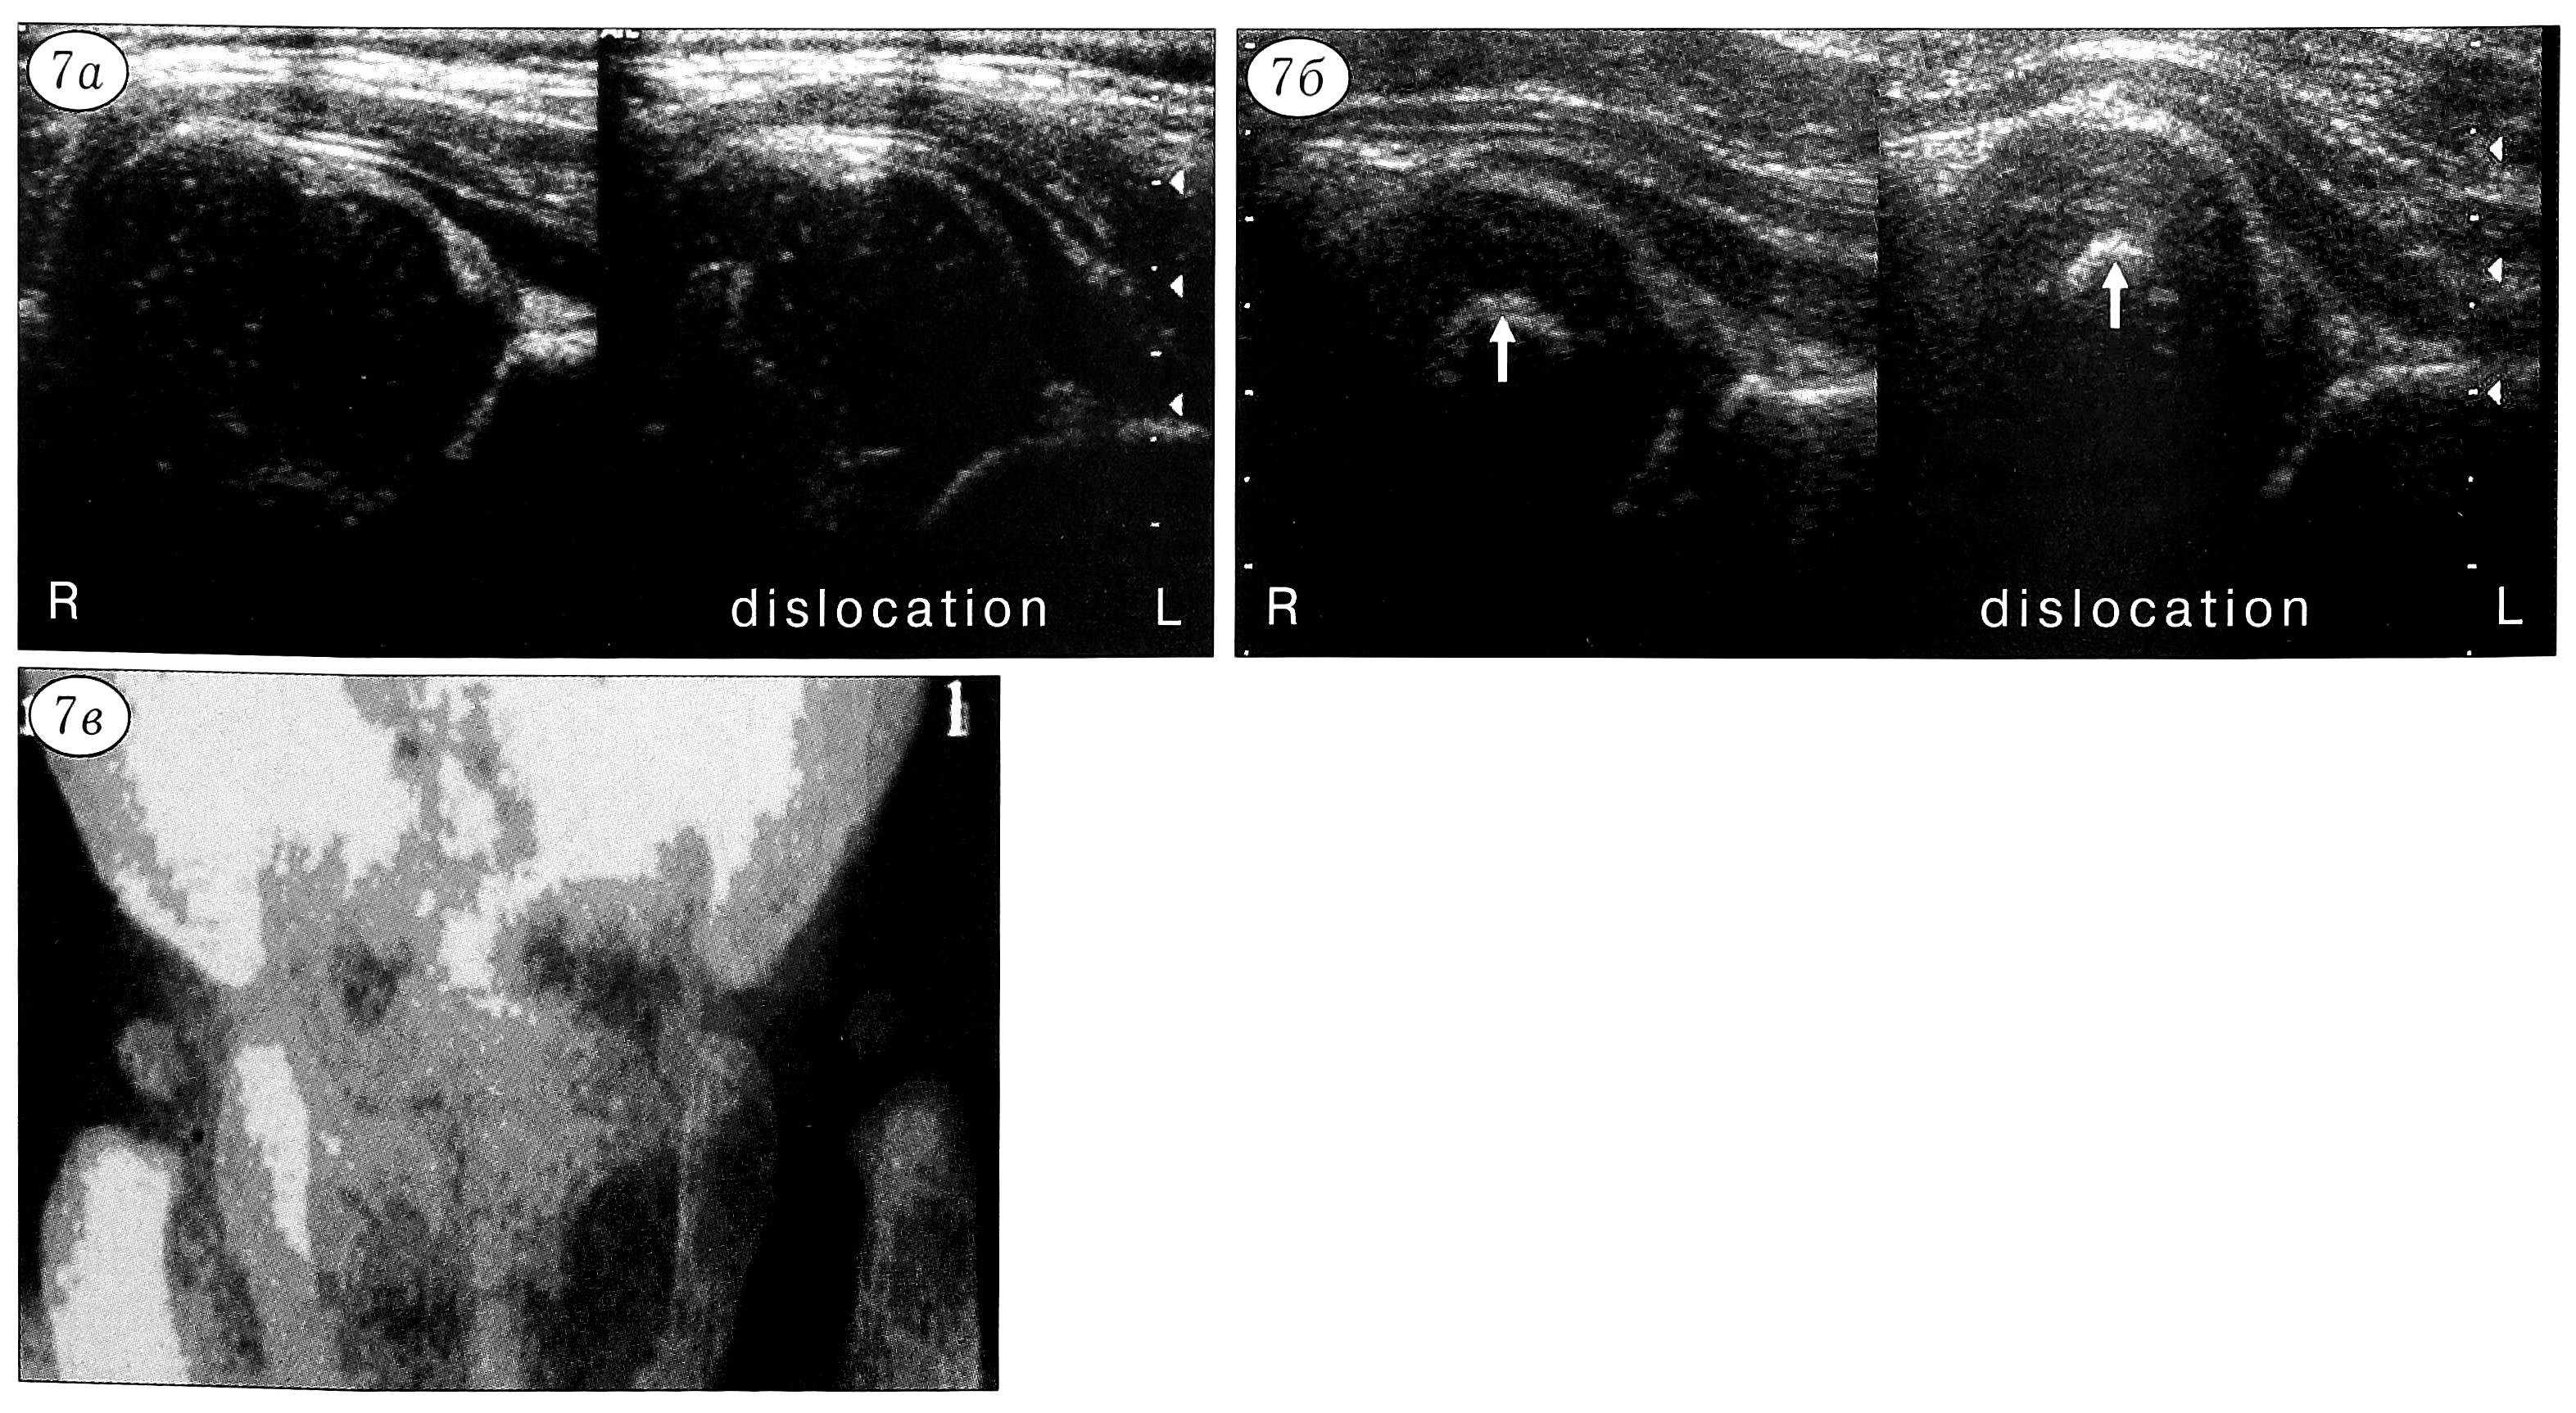

Обследование детей 1-й группы в динамике показало, что при лечении широким пеленанием или стременами Павлика дисплазия тазобедренного сустава у них уменьшалась (нивелировалась в положении отведения конечности — рис. 6), ППГКК через 2-3 мес увеличивался в среднем до 55, все измеряемые параметры приближались к норме.

Рис. 6. Продольные ультрасонограммы ребенка в возрасте 2 мес с дисплазией тазобедренного сустава (стрелками обозначены контуры головки бедра; остальные обозначения те же, что на рис. 3). а — при нейтральном положении конечности головка бедра подвывихнута в латеральную сторону; б — при отведении конечности головка возвращается в вертлужную впадину.